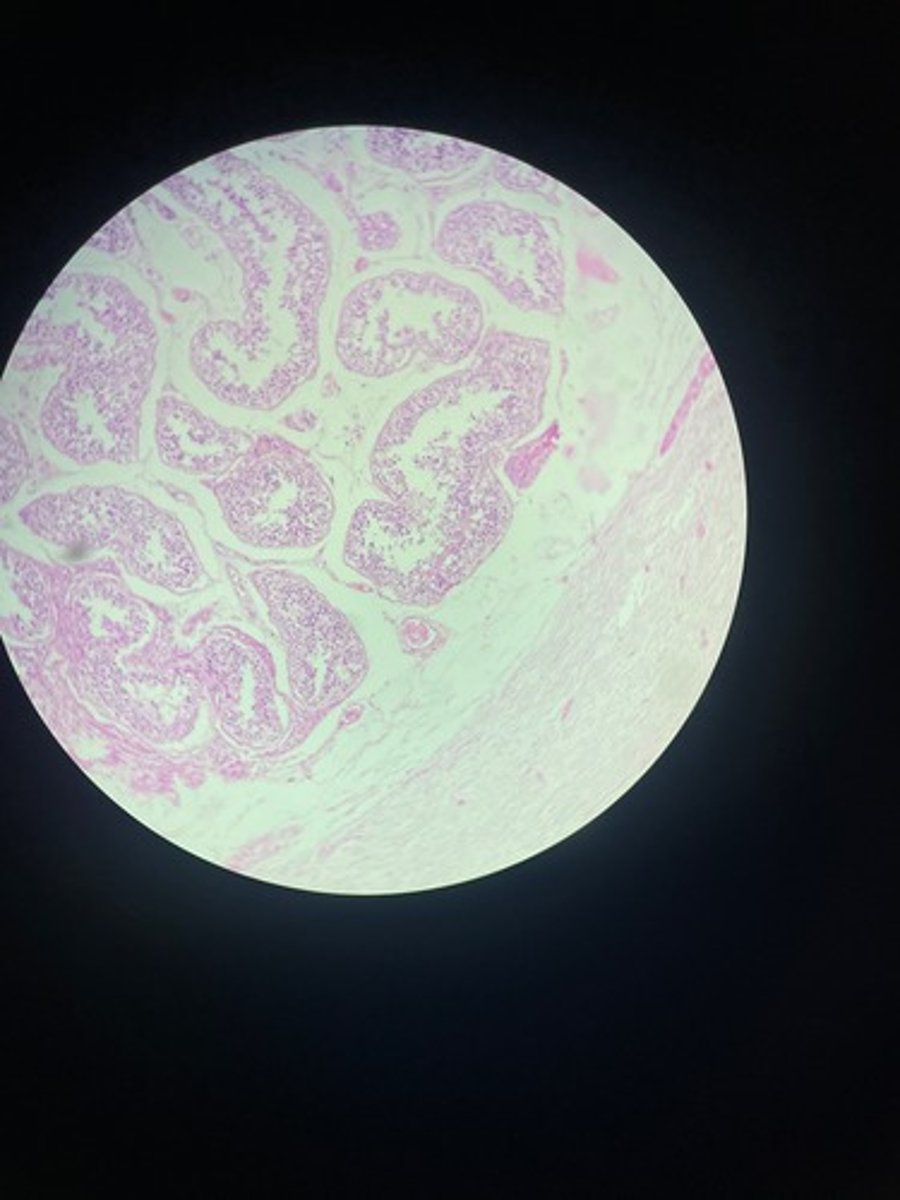

Testes HE

Testes HE

Testes HE

Testes HE

Testes HE